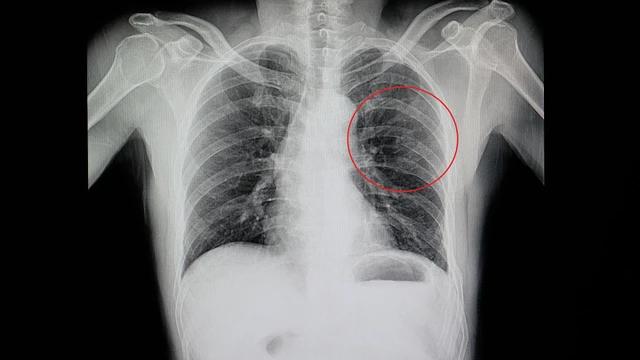

:format(webp)/ran_xuong_suon_0_a776842156.jpg)

Rạn xương sườn là một chấn thương gặp phổ biến ở vùng xương sườn, thường xảy ra khi có va đập mạnh vào khu vực này. Khi xảy ra va chạm hoặc chấn thương, các xương sườn có thể bị gãy hoặc bị rạn nứt. Điều này thường gây ra đau và khó chịu, đặc biệt khi hít thở sâu hoặc cử động cơ thể.